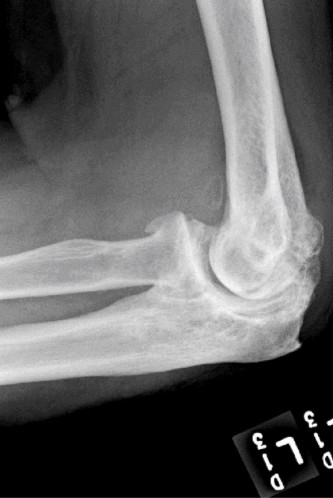

Treat a patient with infected total shoulder arthroplasty? CASE 21 A 70-year-old, right-hand-dominant female presents to clinic complaining of 4 years of gradually worsening chronic right shoulder pain and stiffness. She says the pain is worse at night and with any range of motion, denies a history of trauma, pain in other extremities, or numbness or tingling of the right upper extremity. She notes that her mother suffered from rheumatoid arthritis that affected her shoulder. Physical examination reveals decreased muscle bulk over the right supra- and infraspinatus fossae compared to the contralateral side, limited active and passive ROM, marked weakness with external rotation, and 4+/5 strength with shoulder abduction. X-rays of the right shoulder are shown in Figures 2–58 and 2–59.

Figure 2–58

Figure 2–59

The correct answer is (C). Rotator cuff tear arthropathy consists of a combination of rotator cuff insufficiency, glenohumeral joint degenerative changes, and superior humeral head migration. It is more common in women and also more often found on the dominant side. The patient’s clinical examination with weakened external

rotation and muscle atrophy signaling incompetent supra- and infraspinatus muscles point to rotator cuff insufficiency, and her plain films reveal narrowed glenohumeral joint space as well as superior migration of the humeral head. Choice D is incorrect because, while radiographs would show narrowing of the glenohumeral joint space, they would also likely show numerous osteophytes and posterior wear of the glenoid. Choice B is incorrect because, while adhesive capsulitis does present as decreased active and passive range of motion, the patient’s constellation of symptoms pointing towards rotator cuff insufficiency along with the radiographs make cuff tear arthropathy the more likely choice. Finally, Choice A is incorrect because even though she has a positive family history of rheumatoid arthritis, it is less likely to present only in a single joint. Also, rheumatoid arthritis on radiography appears more as an erosive process without the characteristic superior migration of the humeral head.